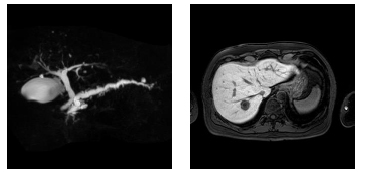

肝の最新MRI 伸弘, 谷本

金原出版

2004/5/1